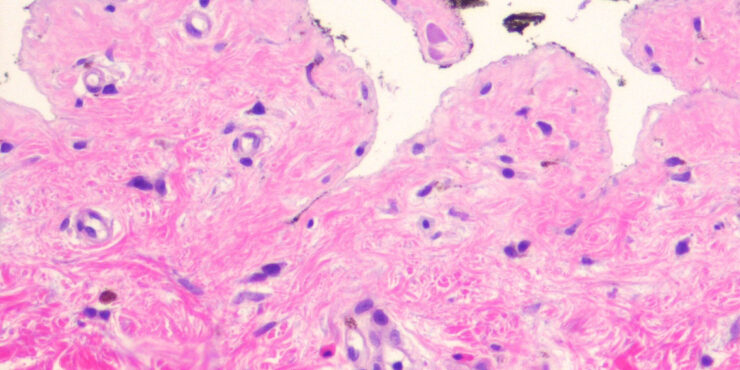

Bullous pemphigoid =الفقاعاني الفقاعي OLYMPUS DIGITAL CAMERA OLYMPUS DIGITAL CAMERA OLYMPUS DIGITAL CAMERA OLYMPUS DIGITAL CAMERA OLYMPUS DIGITAL CAMERA OLYMPUS DIGITAL CAMERA OLYMPUS DIGITAL CAMERA OLYMPUS DIGITAL CAMERA OLYMPUS DIGITAL CAMERA Bullous Pemphigoid First described in 1953 by Lever, bullous pemphigoid affects primarily elderly patients with large tense bullae arising on urticarial erythematous bases or […]